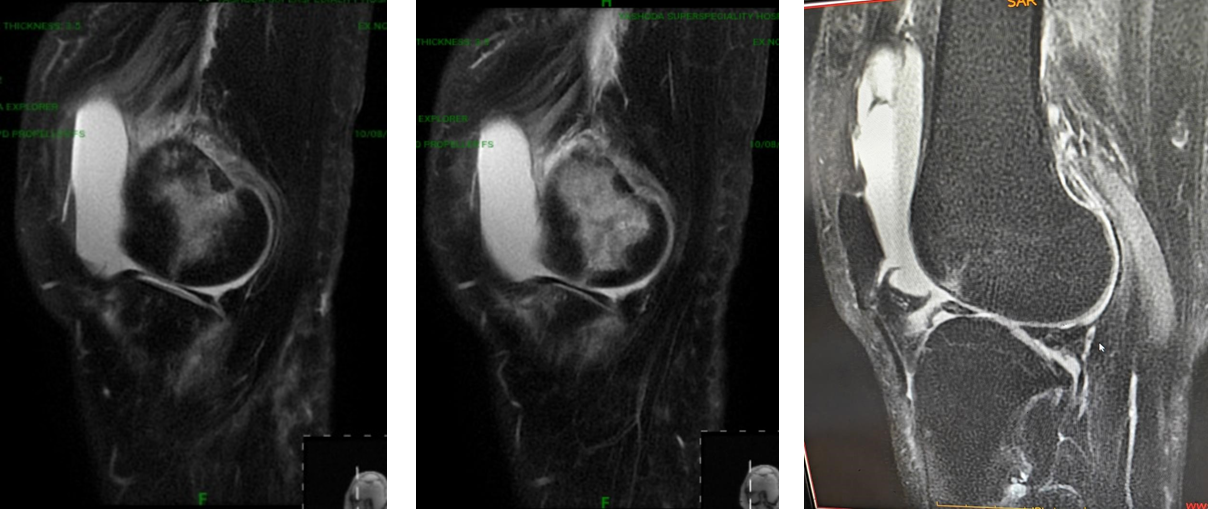

MRI left knee (Figs. 3 and 5) was suggestive of a near-complete ACL tear, a Grade II tear of the anterior horn of the lateral meniscus, and a tear of the medial collateral ligament.

Figure 5: Magnetic resonance imaging scan left knee (Showing tear of anterior horn and part of body of lateral meniscus).